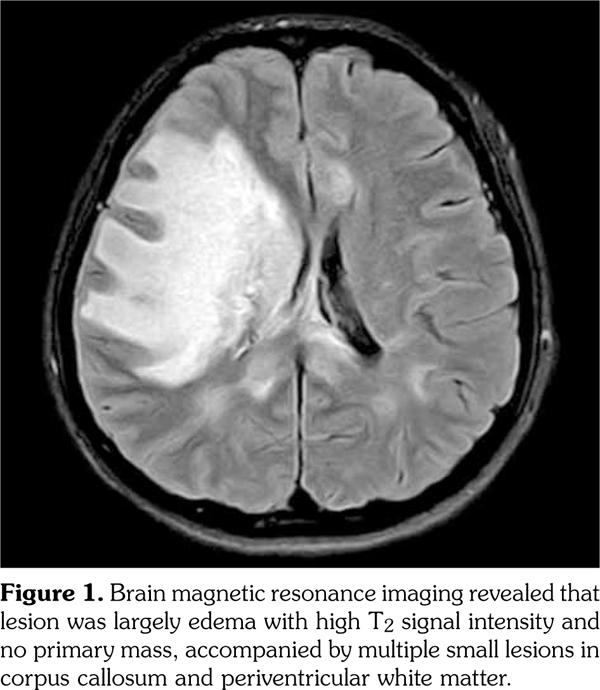

Two weeks after the third cycle of intravenous cyclophosphamide and a reduction of prednisolone to 20 mg, the patient visited the emergency room with a severe headache. However, brain MRI showed no new lesions, only chronic- stage encephalitis with atrophic changes in the previously observed multiple edematous lesions. Two days later, she complained of right-eye pain with a sudden decrease in right visual acuity. Ophthalmological examinations showed a right relative afferent pupillary defect, decreased right visual field, and mild swelling of the right optic disc. Orbital MRI showed interval development of right optic neuritis (Figure 3a, b). Whole-spine MRI showed no evidence of myelitis in the spinal cord. Steroid pulse therapy was administered for three days and plasmapheresis was performed five times. Her vision improved enough for her to read large letters. Results of tests for the anti- AQP4 antibody were positive, and the patient was diagnosed with NMOSD related to pSS. Follow-up orbital MRI after four months showed decreased right optic nerve swelling with disappeared contrast-enhancement, suggesting chronic stage of optic neuritis (Figure 3c, d).